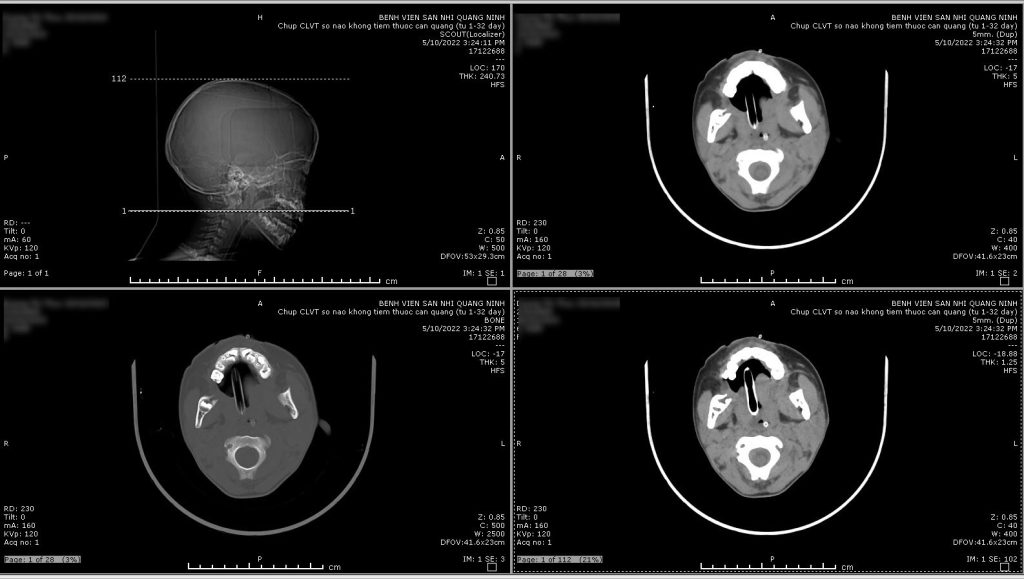

Tối ngày 08/05/2022, Bệnh Viện Sản Nhi Quảng Ninh tiếp nhận bệnh nhi D. T .T 7 tuổi, được chuyển tuyến từ TTYT huyện Bình Liêu trong tình trạng lơ mơ, gọi hỏi không đáp ứng, co giật liên tục khó cắt cơn. Bệnh nhân được xử trí an thần cắt cơn giật, đặt ống nội khí quản, thở máy, chụp cắt lớp vi tính sọ não, chọc dịch não tủy, làm các cận lâm sàng chẩn đoán và được các bác sĩ xác định trong tình trạng động kinh – Viêm não màng não biến chứng phù não lan tỏa 2 bán cầu, tăng áp lực nội sọ nặng/ Viêm phổi/ Tim bẩm sinh thông liên thất/ Suy dinh dưỡng.